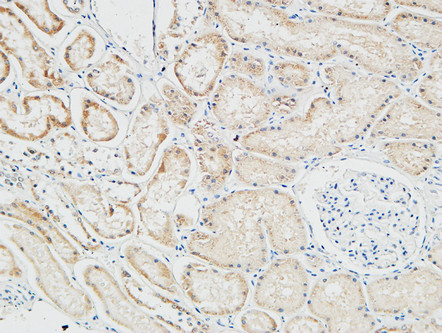

分类: 科研抗体货号: P23194别名: TLR4; Toll-like receptor 4; hToll; CD antigen CD284应用: IHC反应种属: Human,Mouse,Rat